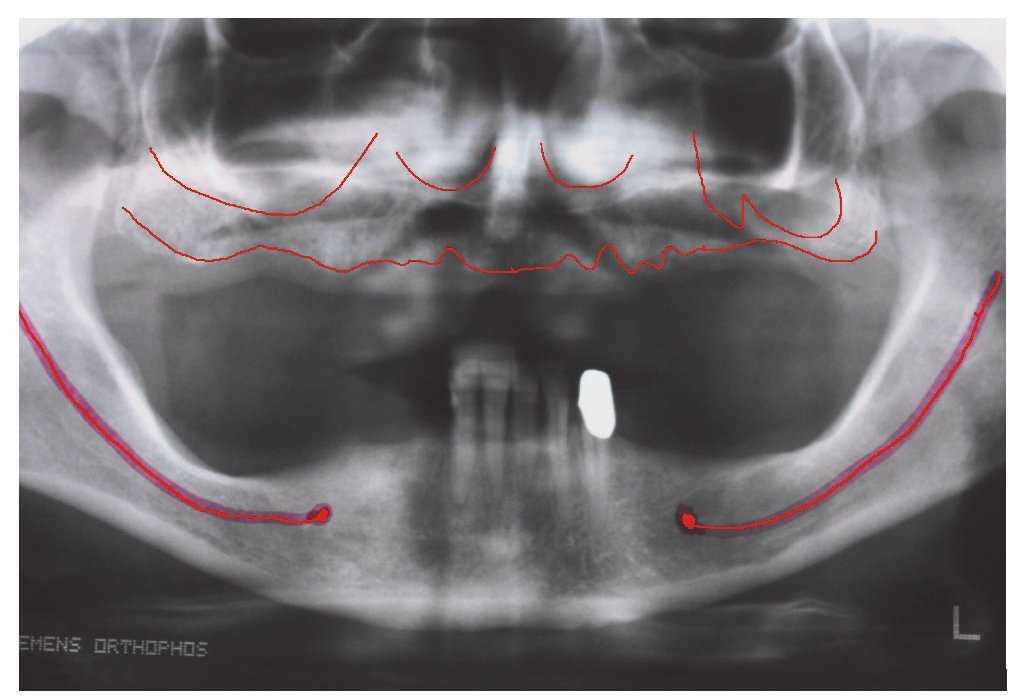

Los métodos de diagnóstico de la consulta dental y una cuidadosa anamnesis del paciente son suficientes para determinar la existencia de uno de los factores mencionados que desaconsejan realizar el tratamiento con implantes en la consulta dental general. Las radiografías intraorales y las radiografías panorámicas son métodos de diagnóstico por imagen ampliamente utilizados en la consulta general. Estos procedimientos pueden combinarse con dispositivos de medición radiográfica integrados que permiten determinar los factores de ampliación y calcular con precisión las condiciones anatómicas verticales del maxilar y la mandíbula. Con el montaje arbitrario de los modelos, la medición del grosor de la mucosa y el segueteado es posible determinar de forma aproximada la dimensión del hueso en sentido horizontal (fig. 2). Este diagnóstico básico es suficiente en pacientes cuya anamnesis no ha arrojado datos reseñables y con una situación correcta del lecho óseo. En cuanto a la realización de diagnósticos por imagen más exhaustivos, la introducción de la tomografía volumétrica digital ha hecho que la radiología dental se adentrara en una dimensión completamente nueva. Dado que este sistema implica una exposición a la radiación mucho menor que la tomografía computarizada helicoidal clásica, es preferible utilizarlo como método de diagnóstico complementario en presencia de relaciones intermaxilares complejas17,21 (fig. 3).

Figura 6. Radiografía panorámica en la que se aprecian claramente déficits de hueso en los sectores posterosuperior y posteroinferior.